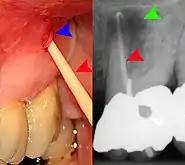

Lateral periodontal abscess (blue arrows) due to a fracture (green arrows)

A periodontal abscess (lateral abscess) is a collection of pus that forms in the gingival crevices, usually as a result of chronic periodontitis where the pockets are pathologically deepened greater than 3mm. A healthy gingival pocket will contain bacteria and some calculus kept in check by the immune system. As the pocket deepens, the balance is disrupted, and an acute inflammatory response results, forming pus. The debris and swelling then disrupt the normal flow of fluids into and out of the pocket, rapidly accelerating the inflammatory cycle. Larger pockets also have a greater likelihood of collecting food debris, creating additional sources of infection.[21]:443

Periodontal abscesses are less common than apical abscesses, but are still frequent. The key difference between the two is that the pulp of the tooth tends to be alive, and will respond normally to pulp tests. However, an untreated periodontal abscess may still cause the pulp to die if it reaches the tooth apex in a periodontic-endodontic lesion. A periodontal abscess can occur as the result of tooth fracture, food packing into a periodontal pocket (with poorly shaped fillings), calculus build-up, and lowered immune responses (such as in diabetes). Periodontal abscess can also occur after periodontal scaling, which causes the gums to tighten around the teeth and trap debris in the pocket.[21]:444–445 Toothache caused by a periodontal abscess is generally deep and throbbing. The oral mucosa covering an early periodontal abscess appears erythematous (red), swollen, shiny, and painful to touch.[22]